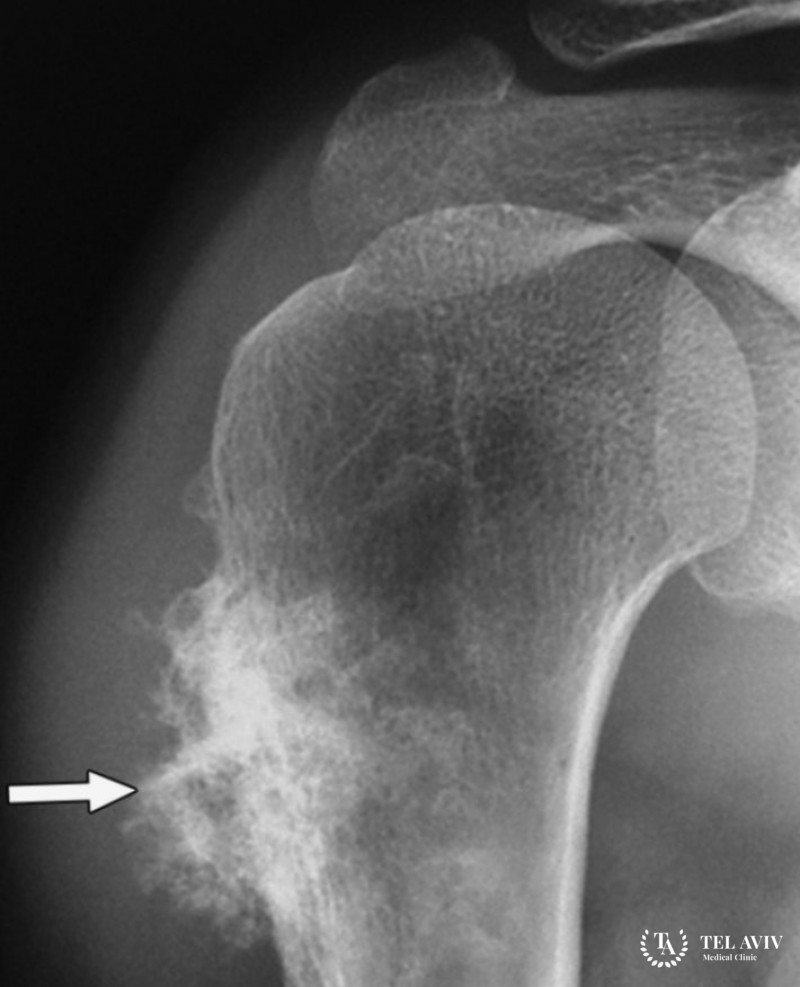

- Рентгена;

Для установки окончательного диагноза необходимо проведение биопсии. Она берется открытым или закрытым способом. Открытый способ предполагает разрез кожных покровов около очага, забор ткани для анализа. Закрытый способ использует длинную тонкую иглу, без разреза.